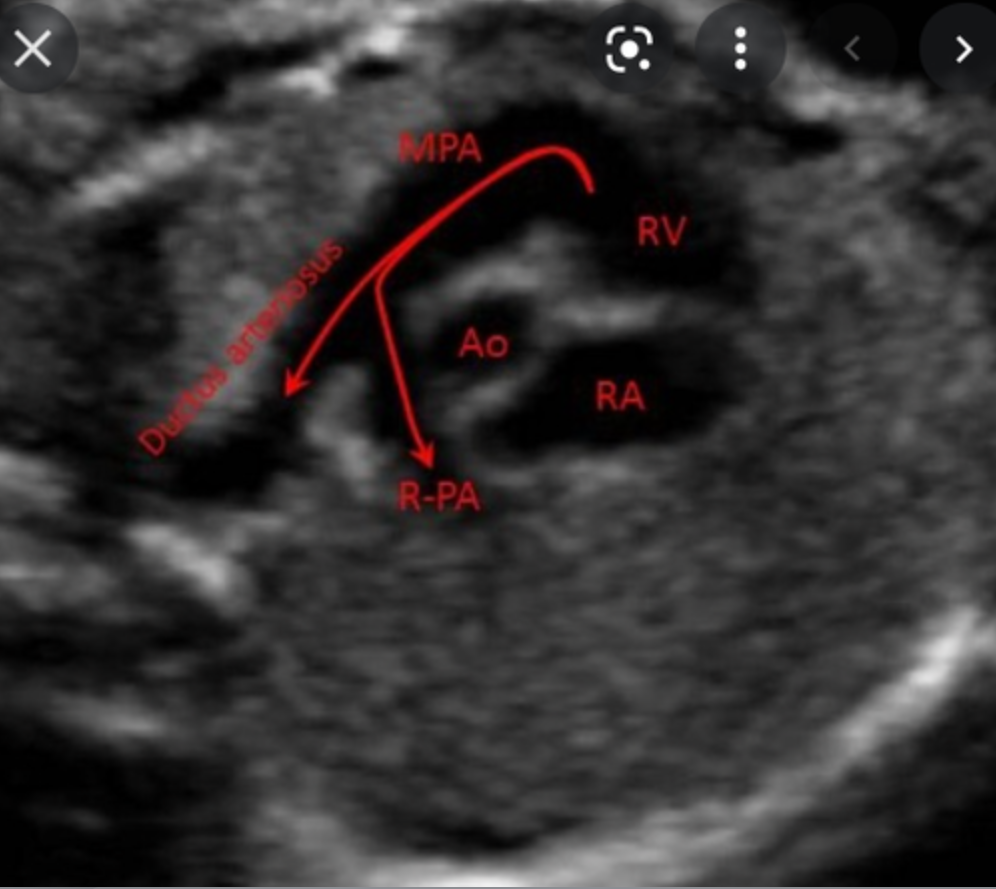

What is RVOT?

connects right ventricle to pulmonary artery

tricuspid; right ventricle; main pulmonary artery (MPA)

MPA bifurcates into right and left pulmonary artery branches that lead to their respective _____

Most of this blood passes through the connection of the ____ _____ into the ____ ____; only a very small amount goes to the lungs

ductus arteriosus; descending aorta